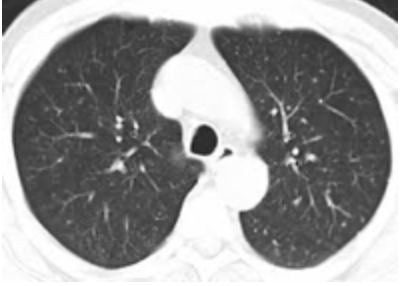

W ARDS, patologii leżącej u podstaw COVID-19, narządem dotkniętym chorobą są płuca, co skutkuje obrazowaniem:

Pęcherzyki płucne są wypełnione powietrzem, (Kolor czarny na obrazie tomografii komputerowej.

Abnormalny skan tomografii komputerowej.

OSTRZEŻENIE, te ilustracje nie są specyficzne dla COVID-19! Widzimy je w przypadkach pneumopatii naciekowej, w tym ostrej hipoksemicznej śródmiąższowej pneumopatii, która może być obecna przy krwotokach wewnątrz pęcherzyków płucnych, pneumopatiach polekowych (amiodaron), toksycznych pneumopatiach i chorobach układu, a także przy zapaleniu naczyń. Należą one do grupy patologii płuc zgrupowanych pod ogólnym terminem ARDS.

Zmiany wyglądające jak zamarznięta, matowa szyba są typowe dla ARDS, a nie dla jakiejś szczególnej przyczyny.

Występują one w szczególności w zakaźnym zapaleniu płuc z tak zwanymi atypowymi zarazkami, takimi jak Mycoplasma Pneumoniae, Chlamydia Pneumoniae czy Legionella Pneumophila, ale także w niezakaźnych pneumopatiach.